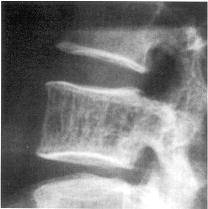

In vertebral lesions, fine or coarse vertical trabeculation is the common appearance with loss of the fine secondary trabeculae. This appearance is mainly found in the vertebral body, but may extend into the neural arch (picture). On MRI, compared with most bony lesions, vertebral haemangiomas show increased SI on T1- and T2-weighted sequences because of their increased fat content. Vertebral haemangioma. (A) CT demonstrates the characteristic appearance of dense ‘dots’ representing the thickened primary trabeculae within a fatty matrix. (B) Coronal T1-weighted MRI in a different patient demonstrating a hyperintense lesion in T10 consistent with the fatty matrix of a haemangioma. (picture)

Radiologic examinations contribute to the diagnosis. On plain X-ray films, the so-called “honeycomb” appearance or coarse vertical striations can be observed, if at least one-third of the vertebral body is involved. Sometimes compression fractures can be seen. The CT scans may show the so-called “polka dot” appearance representing axial cuts caused by thickened vertical trabeculae. MR imaging is helpful for the differentiation between intraosseous (nonevolutive) and extraosseous (more frequently associated with symptomatic lesions) hemangioma. Because of a higher content of fat tissue, intraosseous lesions show an increased signal on T1- and T2-weighted images. Extraosseous lesions contain only little fat and show an isointense signal on T1- and an increased signal on T2-weighted images.